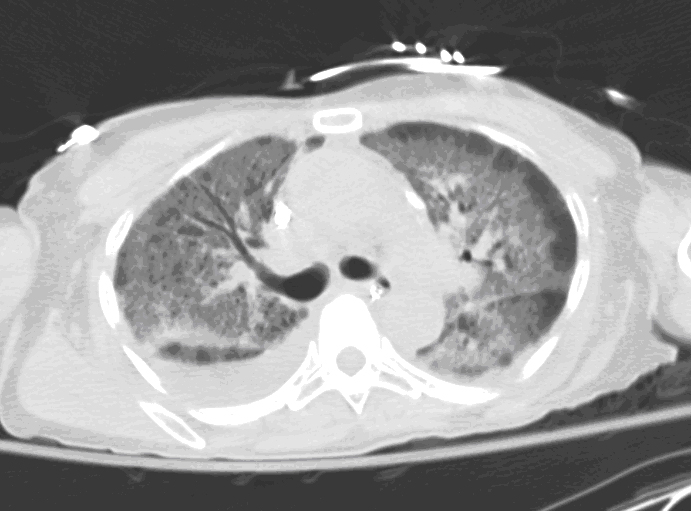

Figure 2: Axial view of high-resolution chest computed tomography (CT) using lung windows showed bilateral diffuse ground-glass infiltrates with peripheral stranding in all lobes.